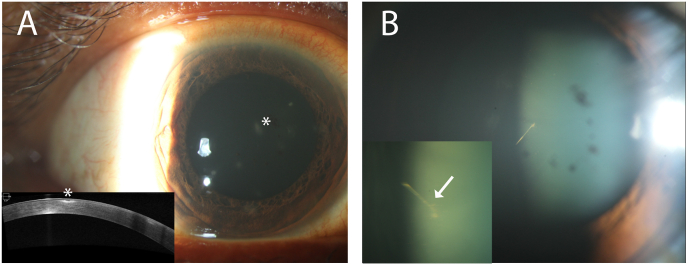

Fig. 1.

A. Slit lamp photograph of the right eye focused anteriorly demonstrates multifocal punctate inflammatory infiltrates in the cornea at presentation (asterisk). Optical coherence tomography (Cirrus, Carl Zeiss Meditec, Inc.) of the anterior segment (bottom left) illustrates subepithelial hyperreflectivity (asterisk) without the presence of retained intracorneal setae. B. Slit lamp photograph of the right eye focused posteriorly shows pigmentary deposits on the anterior lens capsule and a sharp linear structure consistent with a moth seta located in the anterior hyaloid face. The magnified view of the seta (bottom left) shows a different orientation indicating its dynamic positioning within the vitreous cavity. A spine of the seta is visualized (arrow).